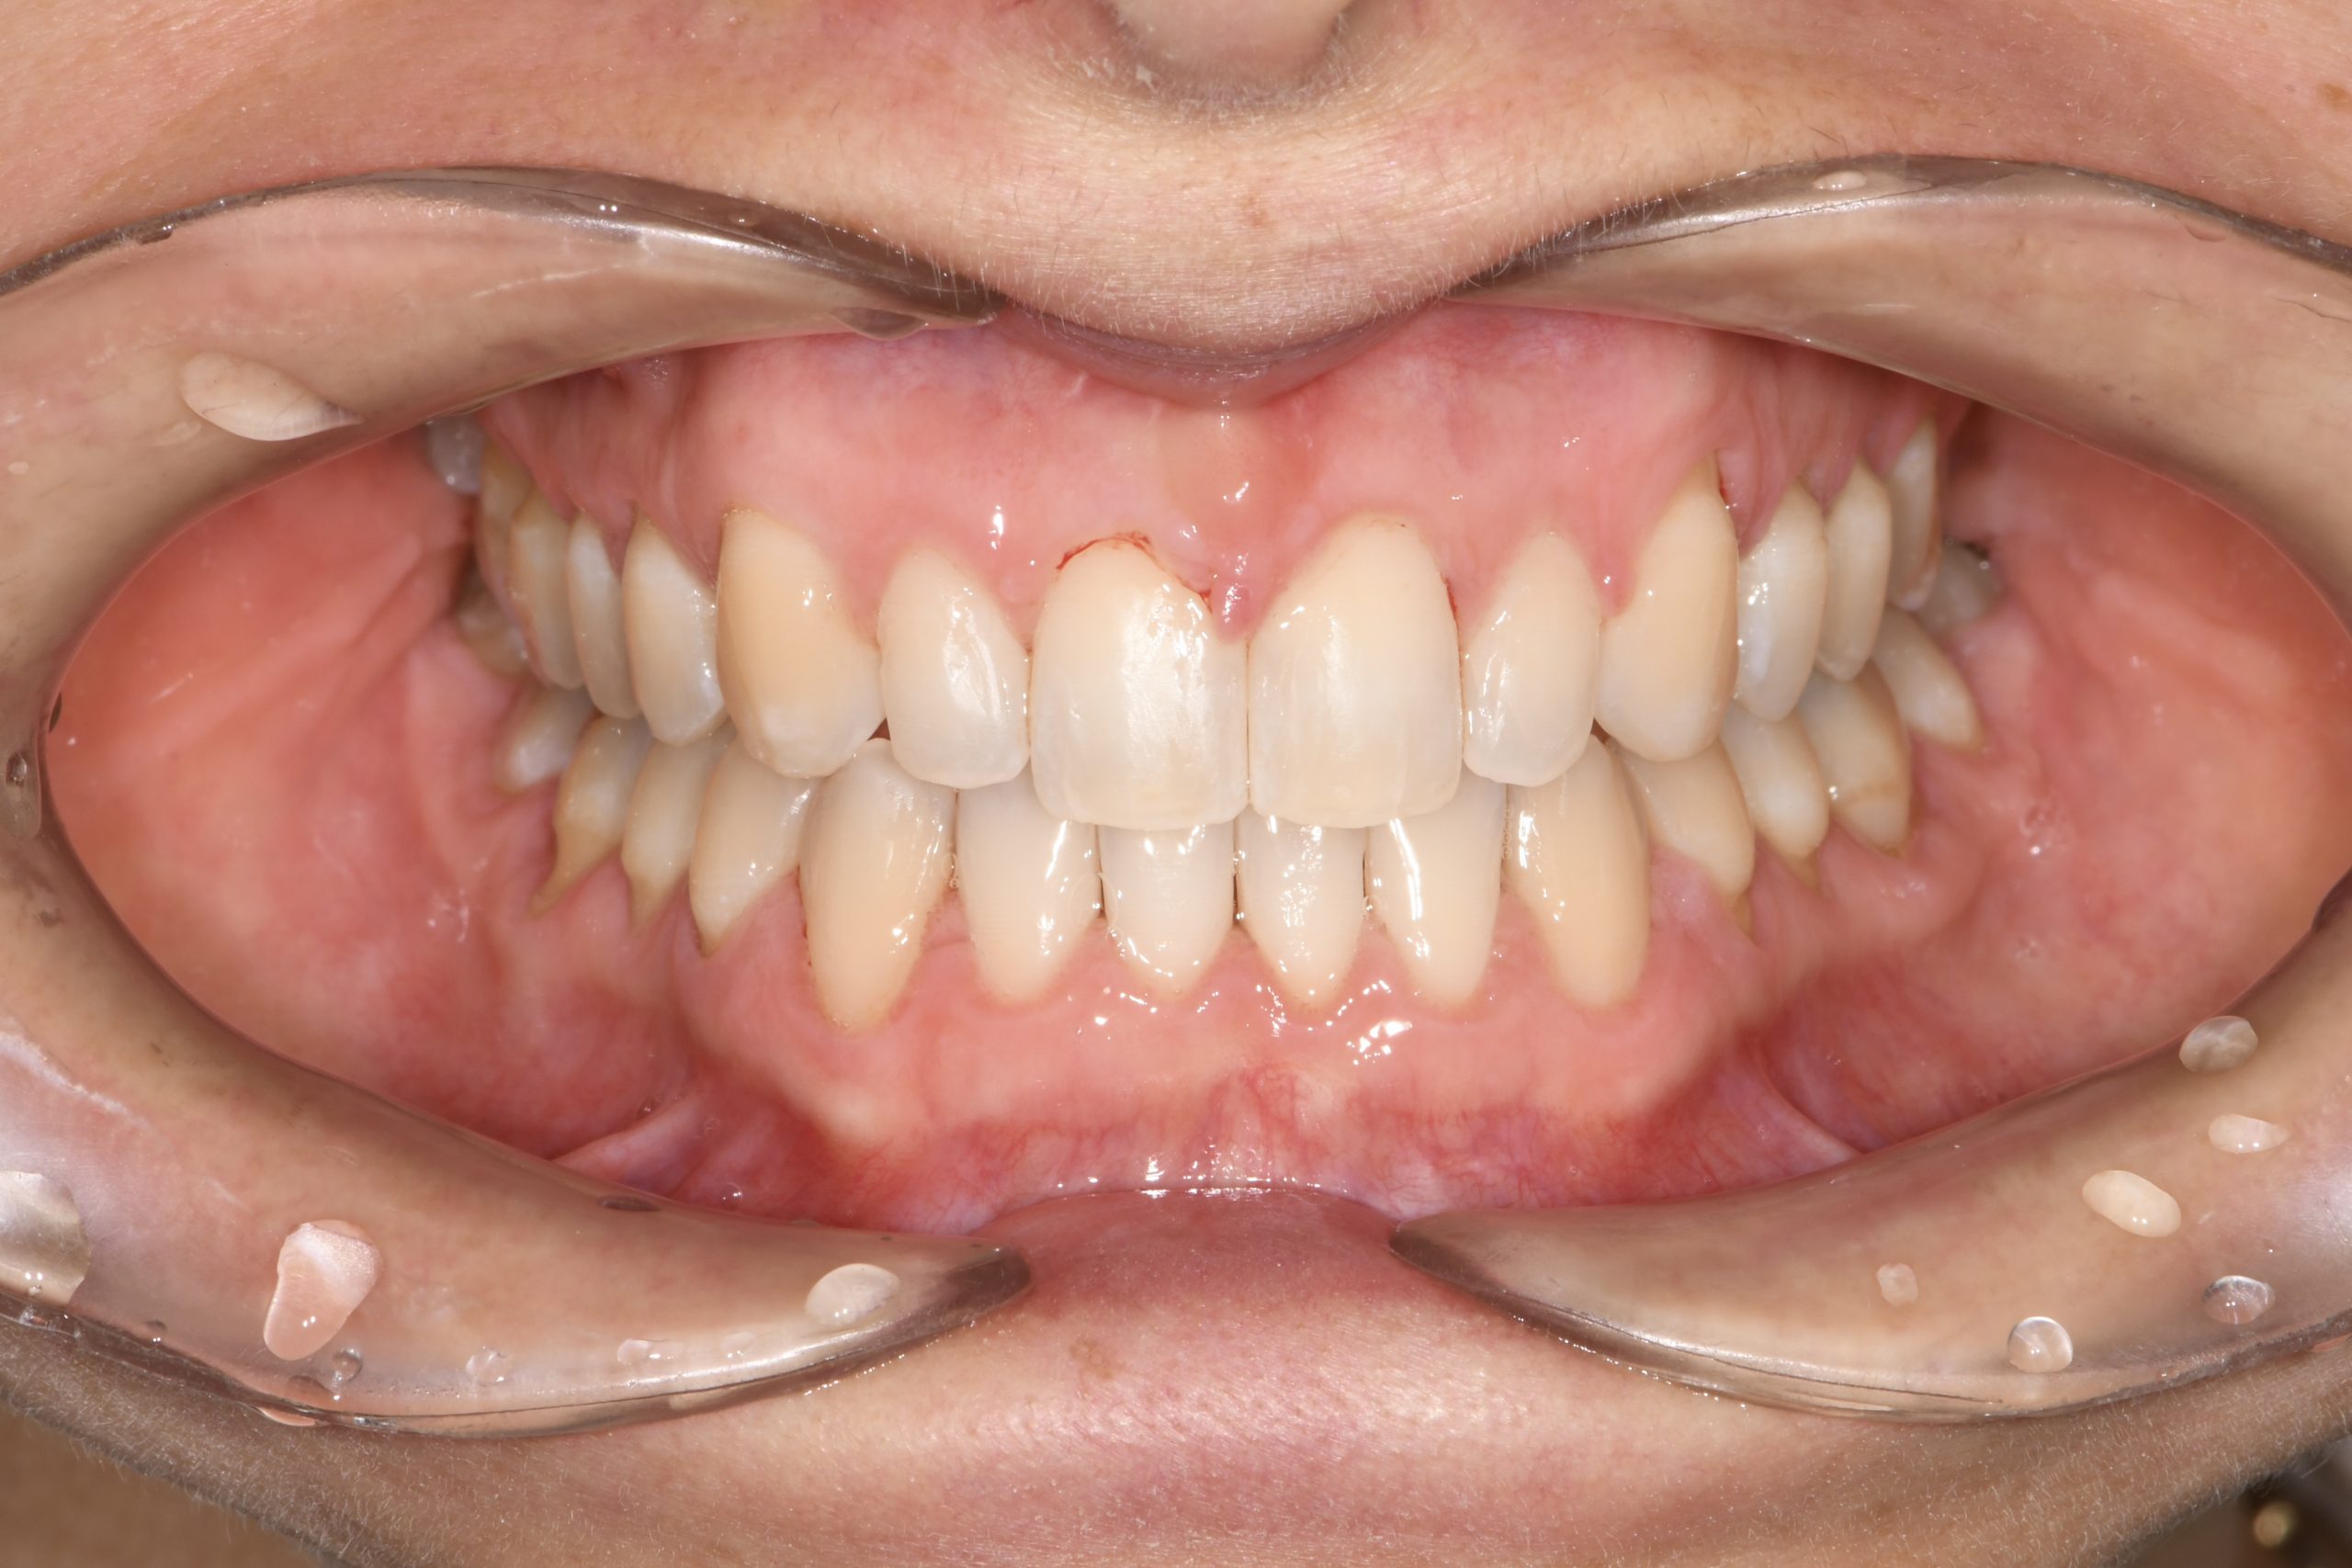

Az elmúlt évekből rengeteg szakmai referenciát tudnánk bemutatni, amelyek különböző fogszabályozási problémákat oldottak meg. Válogatva a több száz esetből, ezen az oldalon olyan képeket, információkat igyekeztünk bemutatni, amelyeknek a segítségével a jövőbeni pácienseinknek azt tudjuk üzenni: A Te fogsorod is lehet gyönyörű!

(Képeket a Pácienseink külön írásos beleegyezésével mutatjuk be!)